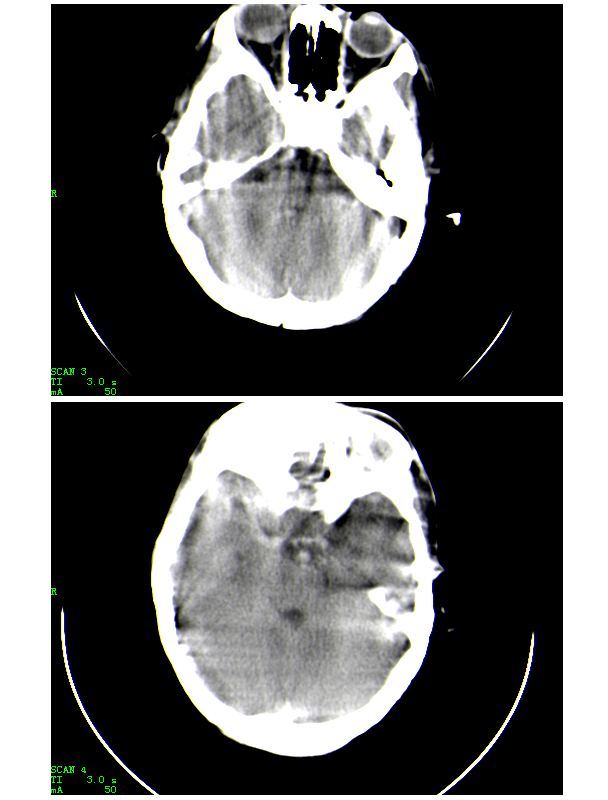

男,13岁,头部外伤后头痛、呕吐三小时就诊,查体,见小孩精神状态尚可,面部,嘴唇青紫明显,后作心脏彩超证实为“发四”,有复查片,大家先看看首诊片,考虑什么

1.有点像强化片背景,考虑为高血红蛋白症;2.脑沟、上矢状窦、小脑幕、大脑脚周围高密度影考虑蛛网膜下腔出血。

1.有点像强化片背景,考虑为高血红蛋白症;2.脑沟、上矢状窦、小脑幕、大脑脚周围高密度影考虑蛛网膜下腔出血

患者,男,15岁。发现心脏杂音12年。因心慌气短、胸闷等症状加重而就诊。急诊实验室检查:红细胞平均体积0.95,红细胞压积0.820,红细胞容积分布宽度0.166,红细胞数8.55x10^12/l,血红蛋白(hb)267g/l。就诊前及就诊期间无外伤史,未服用或注射高密度元素制剂,未行影像造影检查和增强检查。急诊ct平扫示:颅内血管系统边缘清楚,但其内密度明显均匀增高(ct值约73hu),高于脑实质密度,所见颅内脑沟显示边界清楚,脑脊液及脑实质密度属正常平扫密度范围(图1-4)。影像诊断:高血红蛋白脑血管致密改变。

说明:ct值的测定以纯水为0hu,随着水中成分的增加,液体对x线的吸收增加,进而ct值增高。人体血液中影响ct值的主要成分是有形成分红细胞和血浆中的蛋白质,尤其室含铁的hb,其占血液中蛋白质总量的大部分,亦是引起血液ct密度变化的主要因素。hb含量与ct值间具有相关性,noman等的研究表明hb含量每改变10g/l,相应ct值变化为1.86hu。而本例患者的hb高达267g/l,可以解释颅内血管ct值明显升高的原因。本病主要应与蛛网膜下腔出血相鉴别,鉴别要点:(1)本病的高密度血管网络旁仍见清晰、正常低密度脑脊液影;(2)临床没有急性颅内出血的症状何体征。

考虑是高血红蛋白血症,因为从ct上看,密度增高部分都是和颅内血管,静脉窦的走行方向一致的,至于有没有sah,还要靠复查的片子来确定。

感谢大家的关注,本例我们最后诊断为高血红蛋白症所致的脑血管改变,患者血红蛋白258g/l

下面是第二天的复查和受伤后第五天的复查,左侧硬膜下血肿有所吸收,脑内条状高密度无改变